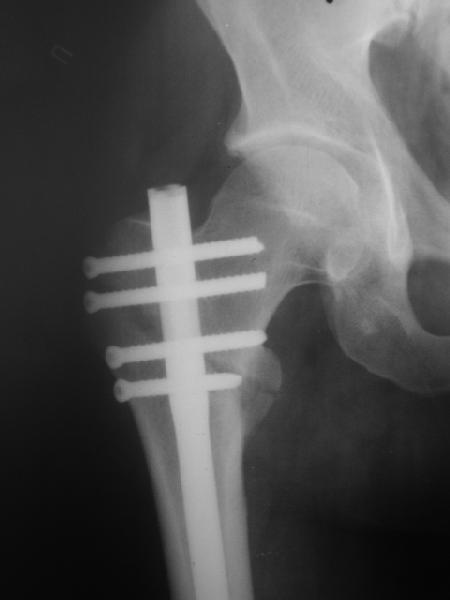

При межвертельных переломах с цефаломедуллярными гвоздями бывает, что проксимальый винт проходит или черед периферический отломок, или прямо над ним. И если остался диастаз, то этот винт при осевой нагрузке не дает сблизиться отломкам. Пример такого остеосинтеза в застарелом случае в приложении.

В частности, на проксимальном конце сделано еще одно дополнительное статическое отверстие. Можно ввести в проксимальном отделе 4 винта, из них 3 статические (2 в круглые отверстия и 1 по нижнему краю овального). Картинки в приложении. На дистальном конце стержня тоже кое-что улучшено. Спрашивайте в аптеках, как говорится. Выпускается предприятием "ЦИТО" (Москва), то есть это малобюджетное решение.

Конечно, мы не синтезируем остеопорозые вертельные переломы согласно прилагаемому примеру, винты 6 мм вырежутся. Но у более молодых при хорошем качестве кости такие или подобные гвозди с поперечным расположением винтов вполне применимы для меж- и подвертельных переломов.

Картинка красивая, но на мой взгляд, не совсем оптимальная: Слишком медиально введён стержень - риск аваскулярного некроза головки бедра.

расположении сопредельных отломков- хорошая локальная васкуляризация. В приведённом случае я бы предпочёл принцип межфрагментарной компрессии (рекон/гамма нэйл 130- 135) принципу шинирования перелома.

Женя, эта картинка показывает не оптимальное лечение вертельных переломов в моем представлении, а особенности дизайна упомяутого фиксатора.

В частности, его возможности при фиксации переломов проксимального отдела бедра - в сравнении с другими, имеюшими лишь по одному статическому и динамическому отверстию и с кондуктором для введения 2 винтов.

Это было года 2,5 назад, мы тогда еще уточняли возможности шинирования с угловой стабильностью гвоздем с поперечным расположением винтов при переломах проксимального отдела бедра. Пациенту не пришлось приобретать намного более дорогой рекон или проксимальный гвоздь. В приложении еще несколько примеров применения того гвоздя при высоких переломах бедра, в том числе с более латеральной точкой входа. Гвоздь изгибаем для этого.